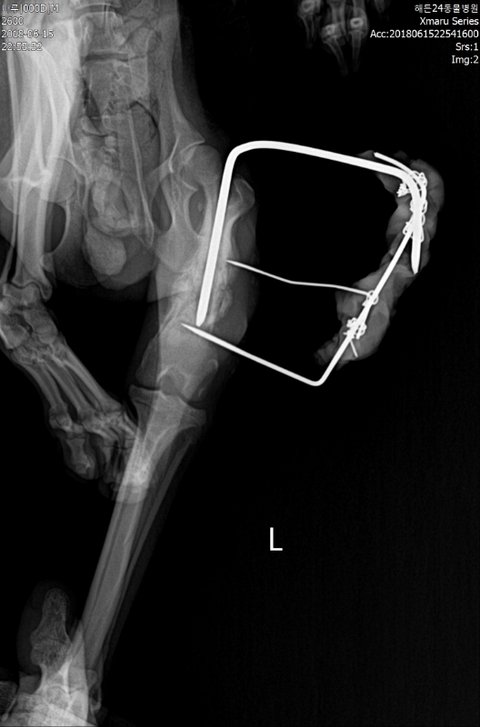

몸무게2.8키로/PSS(소간증)/예전홍역의심/골절수술부위2차감염/빈혈/탈수/저체중/저체온/눈궤양/암모니아,신장,칼슘,거의 모든수치 이상/이빨멜라닌색소소멸/위장음식물없음등을 알게됐습니다.

다리는 골수염으로 염증이 심각했고, 절단가능성이 계속 이야기되었지만 기적적으로 염증을 6ml 뽑아낸후 항생제 예후가 좋아 다행히 좋아지고있는 상태입니다. 하지만 아직 금이 가있고 내원치료중입니다..

초진 엑스레이입니다.